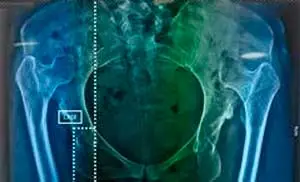

Especialista en cadera y pelvis

Cirugía de Cadera y Pelvis, en la Universidad Nacional Autónoma de México (UNAM).

Mediciones radiográficas de la orientación del componente acetabular con el método de Wid…